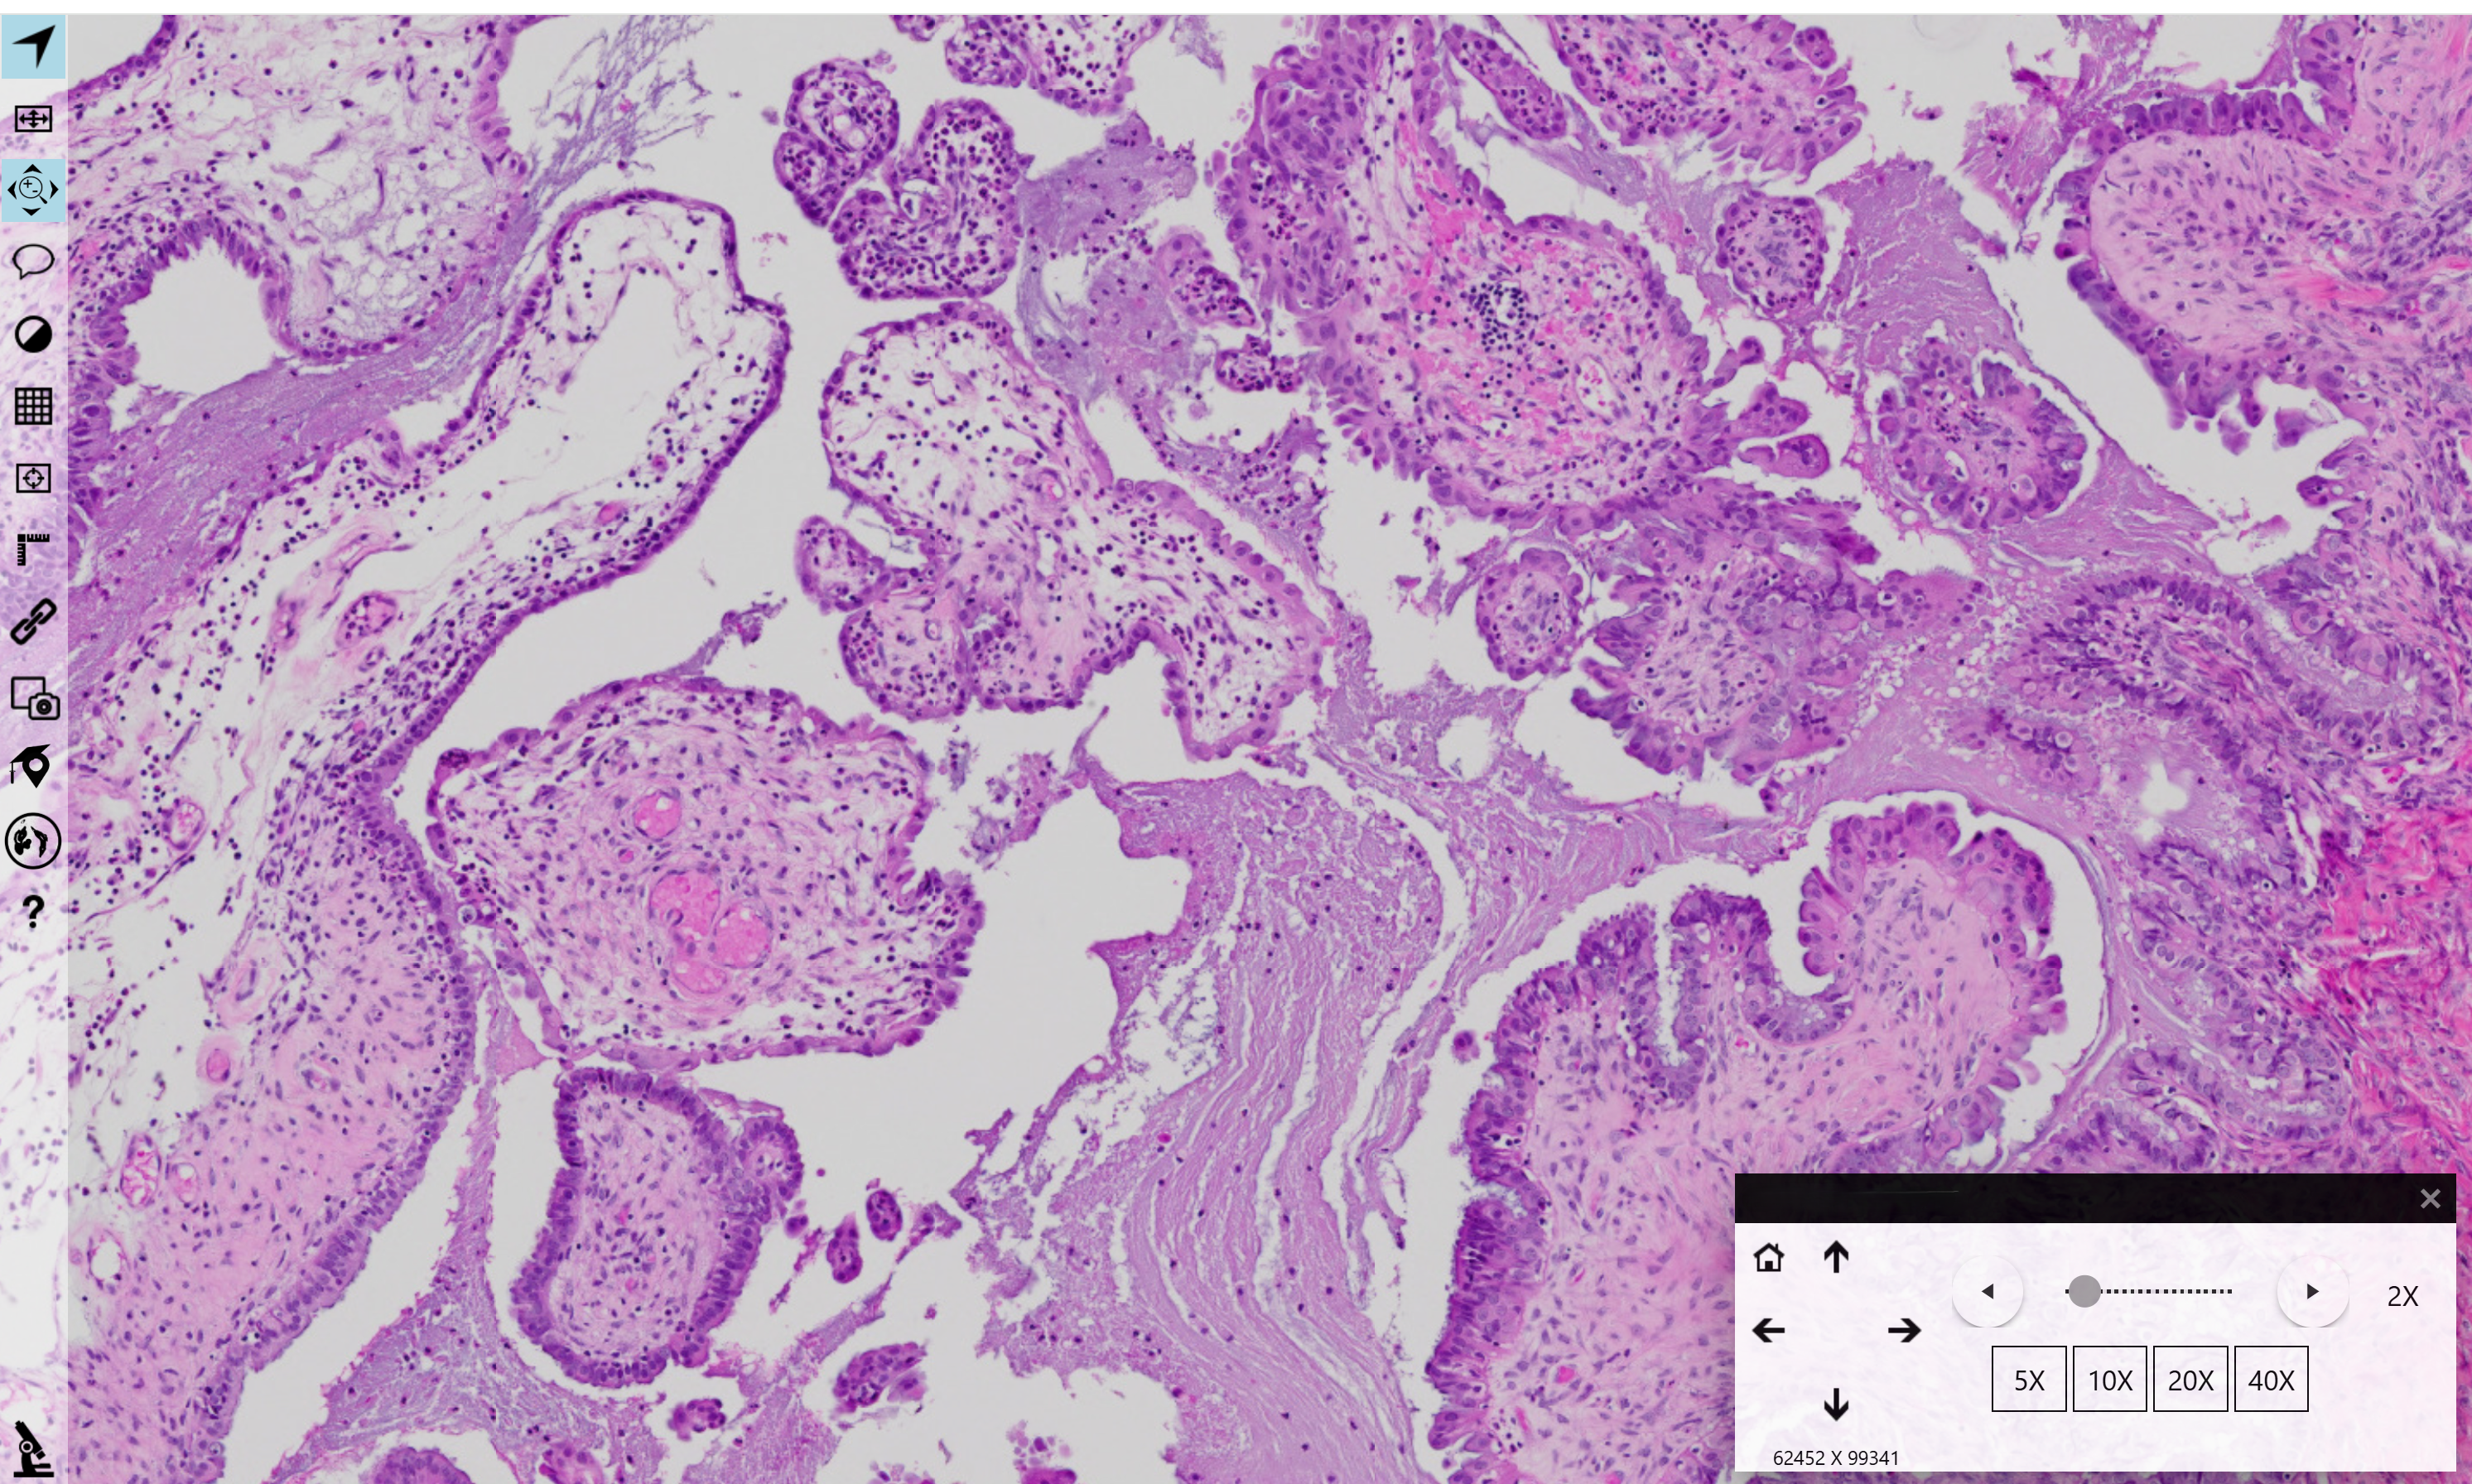

Diagnostic Pathology Second Opinions

Second opinions and consultative diagnostic pathology services with emphasis on accuracy, clarity, and clinical relevance.